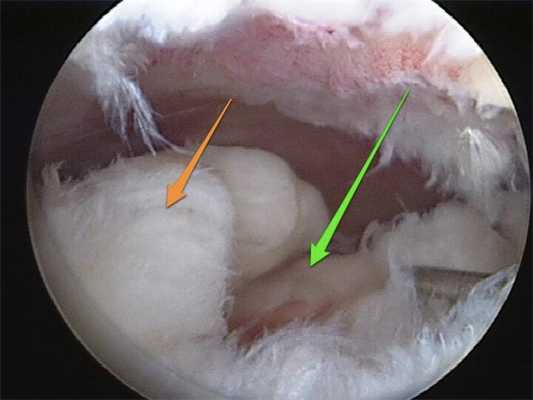

Разрыв внутреннего мениска по типу «ручки лейки» с блоком коленного сустава (невозможность полностью разогнуть коленный сустав). На фотографии хорошо виден крупный фрагмент мениска плотно зажатый между суставными поверхностями бедренной и большеберцовой кости.

Дегенеративный комбинированный разрыв тела и заднего рога внутреннего мениска коленного сустава.

Продольный разрыв заднего рога наружного мениска, сопровождающийся его гипермобильностью. При таком разрыве мениск может значительно смещаться внутрь сустава создавая ощущение механического блока, инородного тела, нестабильности в суставе, заклинивания, щелчков.

Удалённый фрагмент внутреннего мениска при разрыве по типу ручки лейки с блоком коленного сустава.

Мениск после обработки по поводу паракапсулярного субтотального разрыва по типу ручки лейки.